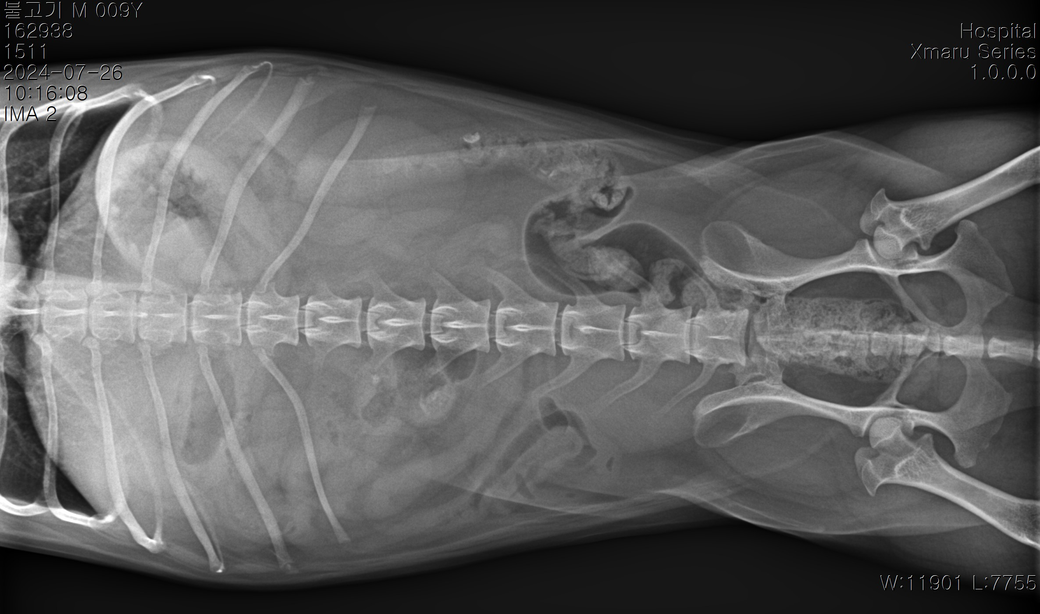

순차적으로 고관절 에 관해 봐주시기 부탁드립니다.

3 사진이 순차적입니다 순차적으로 고관절에 큰 변화가 있나요?

마지막 보여지는 부분에서 오른쪽 고관절이 탈구된거라고 하는데 이전 사진에서는 탈구가 안되었나요?

마지막 사진은 촬영할때 환자가 몸을 꼬아서 뒤틀려진 고관절이 찍힌 사진으로 이 사진으로는 고관절 탈구를 평가하면 안됩니다. 앞 사진에서는 탈구가 관찰되지 않고, 특히 연골이형성품종에 해당하는 환자이기 때문에 정상범주가 매우 높습니다. 주치의의 상담을 받으시기 바랍니다.